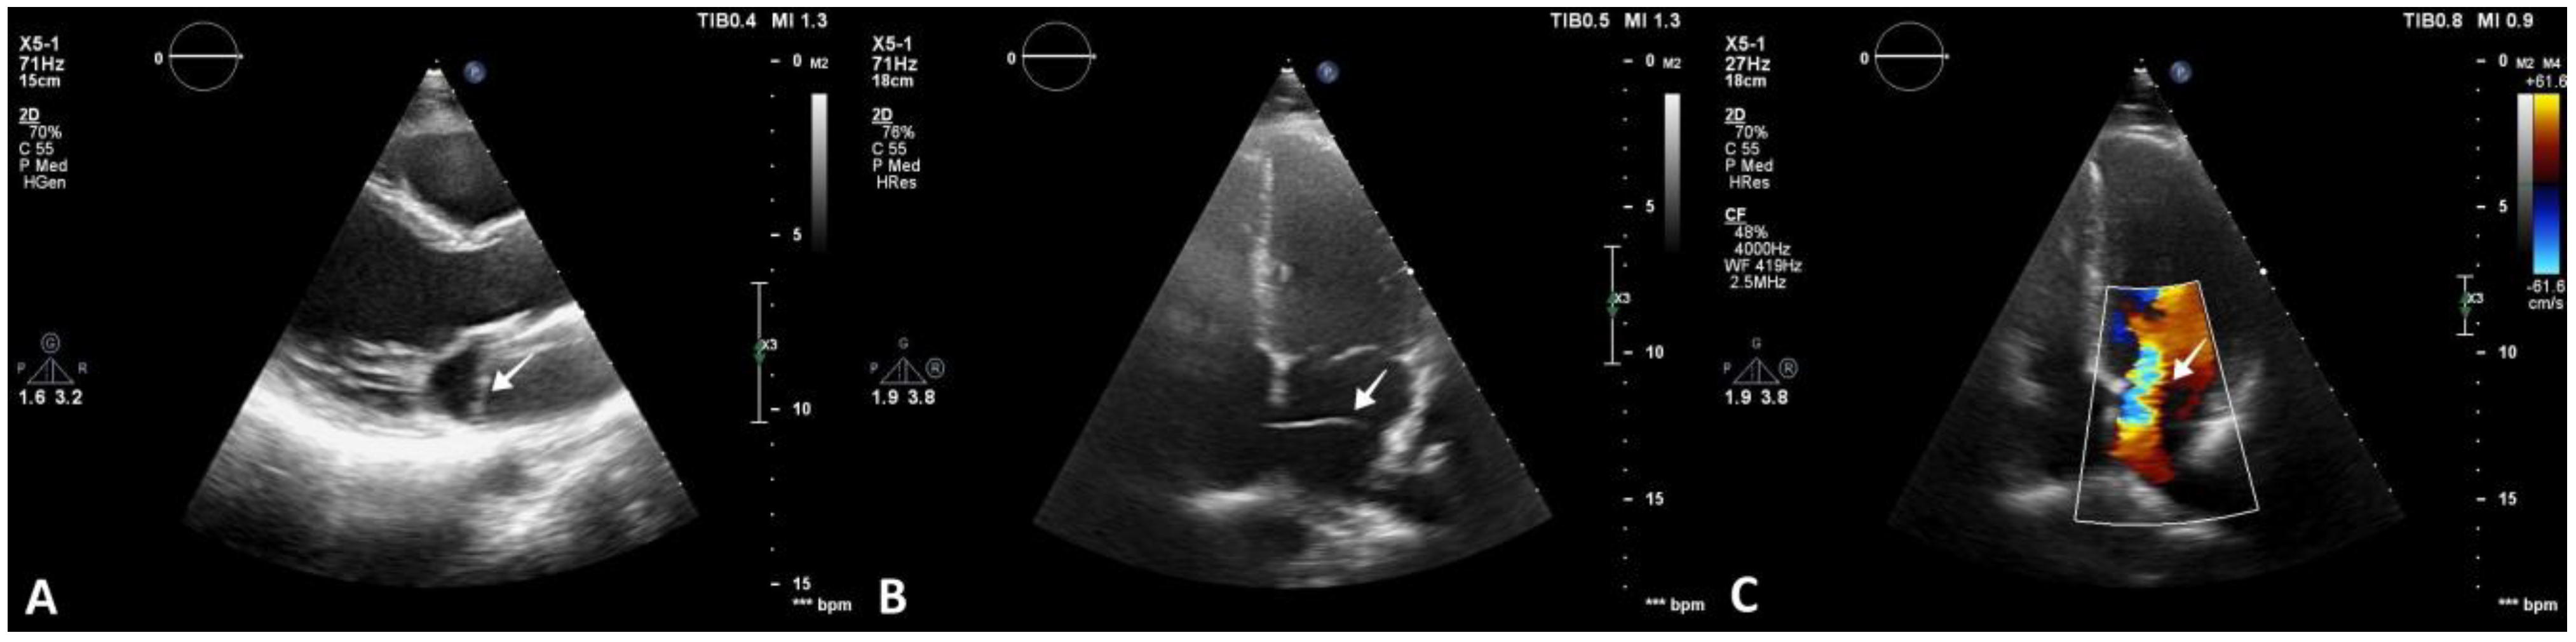

The patient denied having a family history of cardiovascular disease and symptoms of cardiac origin. She had an unremarkable medical history, and her physical examination was normal. Resting 12-lead electrocardiogram showed sinus rhythm with normal heart rate and no morphological anomalies. As part of the diagnostic work-up, transthoracic echocardiography was also carried out, revealing normal cardiac chamber size, left and right ventricular function, and no valvular heart disease. An echodense structure was identified bisecting the LA horizontally into postero-superior and antero-inferior parts. No significant pressure gradient was detected using continuous Doppler across the flexible membrane in the four-chamber view (Figure 2).

Figure 2.

Transthoracic echocardiography revealing CTS. (A) Parasternal long-axis 2D view showing an echodense, membranous structure within the LA (arrow). (B) Apical four-chamber 2D view showing the membrane bisecting the LA (arrow). (C) Apical four-chamber 2D view and color Doppler window placed over the LA, highlighting turbulent flow across the membrane (arrow).